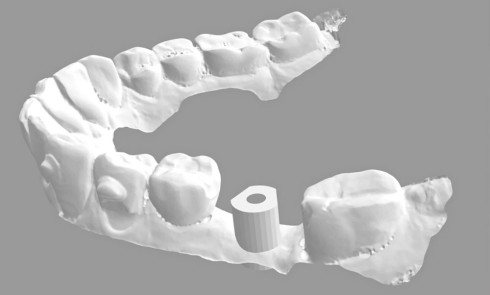

Confection de la prothèse d’usage : la prothèse transitoire est restée deux mois en bouche, jusqu’à l’intégration fonctionnelle et la satisfaction esthétique de la patiente [13,14]. Puis, la prothèse d’usage est confectionnée, en commençant par la réalisation de l’armature métallique au laboratoire (fig. 13a-h).